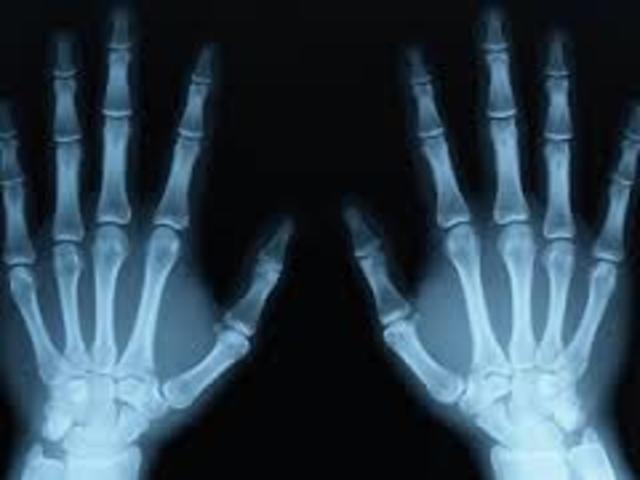

• lops rayos x

lops rayos x

Wilhelm Roentgen descubre accidentalmente los rayos X al realizar experimentos con la radiación de rayos catódicos (electrones). Se da cuenta de que los rayos pueden penetrar en papel negro opaco envuelto alrededor de un tubo de rayos catódicos, causando una forma que brilla con fluorescencia.